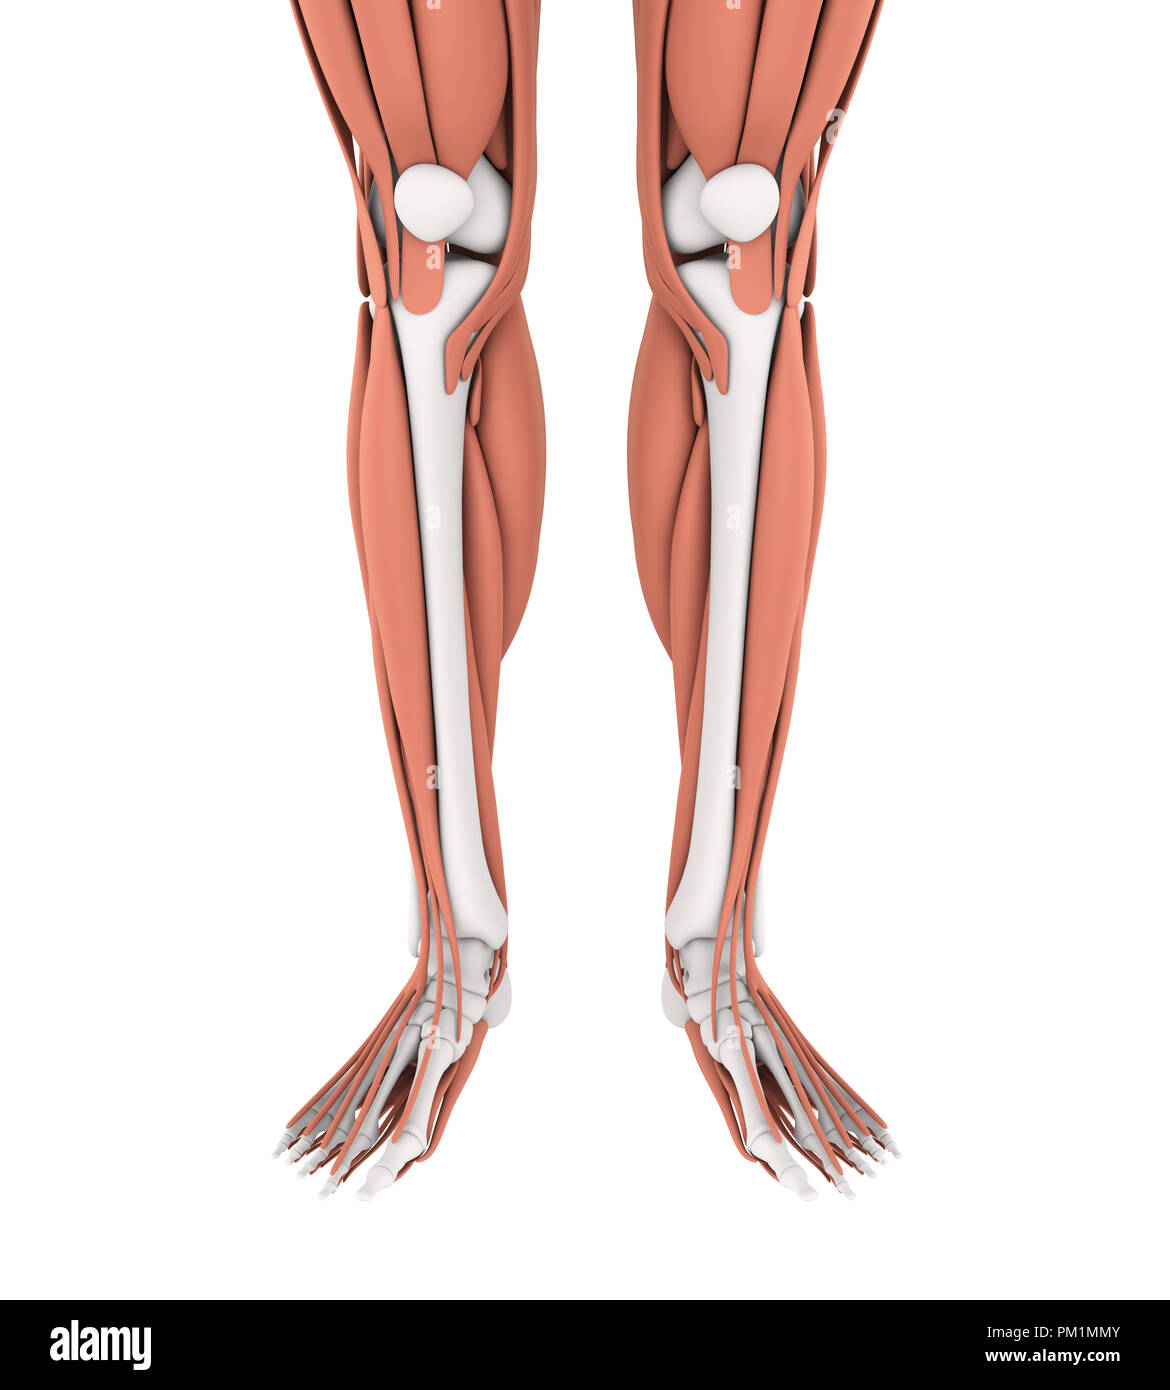

Muscle anatomie de l'homme les droits de l'jambes, vue antérieure. Banque D'Imageshttps://www.alamyimages.fr/image-license-details/?v=1https://www.alamyimages.fr/photo-image-muscle-anatomie-de-l-homme-les-droits-de-l-jambes-vue-anterieure-59361114.html

Muscle anatomie de l'homme les droits de l'jambes, vue antérieure. Banque D'Imageshttps://www.alamyimages.fr/image-license-details/?v=1https://www.alamyimages.fr/photo-image-muscle-anatomie-de-l-homme-les-droits-de-l-jambes-vue-anterieure-59361114.htmlRFDCG3KP–Muscle anatomie de l'homme les droits de l'jambes, vue antérieure.

Muscle anatomie de l'homme les droits de l'jambes, vue antérieure. Banque D'Imageshttps://www.alamyimages.fr/image-license-details/?v=1https://www.alamyimages.fr/photo-image-muscle-anatomie-de-l-homme-les-droits-de-l-jambes-vue-anterieure-59361136.html

Muscle anatomie de l'homme les droits de l'jambes, vue antérieure. Banque D'Imageshttps://www.alamyimages.fr/image-license-details/?v=1https://www.alamyimages.fr/photo-image-muscle-anatomie-de-l-homme-les-droits-de-l-jambes-vue-anterieure-59361136.htmlRFDCG3MG–Muscle anatomie de l'homme les droits de l'jambes, vue antérieure.

L'anatomie les muscles des jambes Banque D'Imageshttps://www.alamyimages.fr/image-license-details/?v=1https://www.alamyimages.fr/l-anatomie-les-muscles-des-jambes-image218855753.html

L'anatomie les muscles des jambes Banque D'Imageshttps://www.alamyimages.fr/image-license-details/?v=1https://www.alamyimages.fr/l-anatomie-les-muscles-des-jambes-image218855753.htmlRFPM1MMW–L'anatomie les muscles des jambes